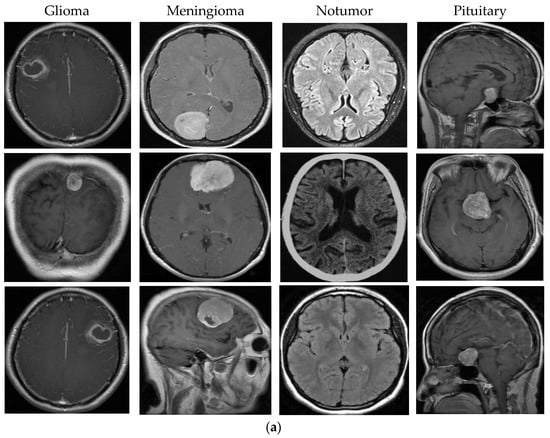

In this study, a publicly accessible dataset was acquired from kaggle.com by merging images from the Br35H, SARTAJ, and figshare datasets [25]. Each image is a 512 × 512 jpeg file. The dataset includes MRI scans of glioma, meningioma, notumor and pituitary brain tumor types. The dataset contains 7023 images in total, consisting of 1311 test data and 5712 training data. The number of training and test MRI images for each class is detailed in Table 1. Figure 2 shows sample images for each class in the dataset.

Figure 2.

Sample images from dataset.